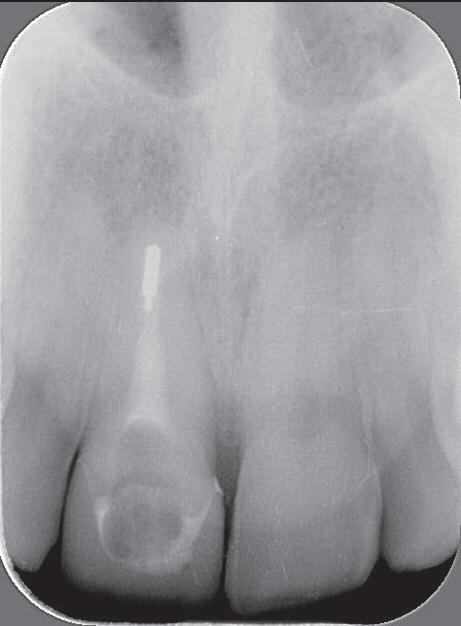

Een 47-jarige collega presenteert zich in onze verwijspraktijk voor endodontie. Hij heeft enige tijd geleden zijn kroon op de 11 laten vervangen (afbeelding 1). Omdat er geen klinische en röntgenologische aanwijzingen waren voor een periapicale laesie of een insufficiënte wortelkanaalbehandeling van de 11, werd besloten de endo, die dateerde van meer dan 30 jaar geleden, niet te reviseren (afbeelding 2). Tijdens een routinematige gebitsreiniging constateert zijn mondhygiënist een pocket van 7 mm aan de mesiopalatinale zijde van 11 (afbeelding 3). De nieuwe kroon wordt tijdelijk gecementeerd, en omdat

1: Klinische foto van bovenfront

2: Röntgenfoto van 11 met zilverstift sectie

Er wordt een CBCT gemaakt die een laesie aan de mesiopalatinale zijde van 11 laat zien (afbeelding 4).

Zes weken later komt de patiënt terug voor evaluatie. Hij heeft de indruk dat de conditie van zijn tandvlees aanzienlijk is verbeterd, de centrale papil is steviger geworden, en er is minder bloeding. De pocketdiepte is met 2 mm afgenomen. We besluiten om de wortelkanaalvulling aan te brengen, waarna de bestaande ruimte boven de kanaalvulling wordt opgevuld met twee glasvezelstiften (afbeelding 8-10) en een composietopbouw. Daarna wordt de kroon definitief gecementeerd (afbeelding 11-12).

9: Röntgenfoto met kanaalvulling en twee glasvezelstiften

13: Röntgenfoto van 11 na 3 jaar

14: Pocket tot 4 mm gereduceerd na 3 jaar

17: Follow-up na 14 jaar

Bij de controle na 3 jaar (afbeelding 13) is de pocketdiepte verder afgenomen tot 4 mm (afbeelding 14), de gingiva is stevig en er is geen bloeding na sonderen. De CBCT laat duidelijk ingroei van het bot zien (afbeelding 15 en 16). De laatste röntgenfoto dateert van 14 jaar na de behandeling (afbeelding 17), er zijn geen klachten en de parodontale conditie is stabiel.